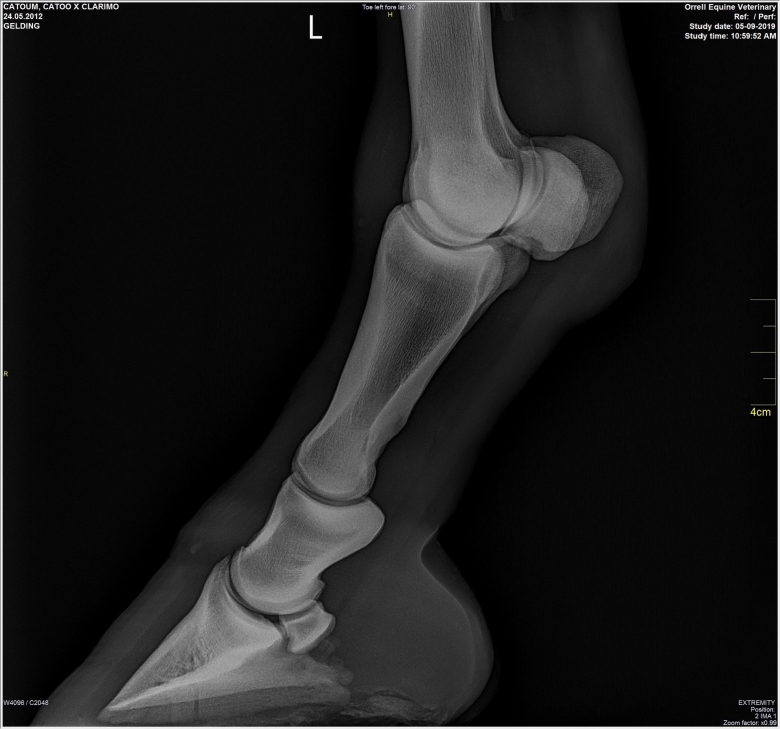

Snart dök det även upp röntgenplåtar, utan att Marina ens hade frågat efter dem. Röntgenbilderna skickade Marina vidare till två olika veterinärer för bedömning. Bägge såg lösa benbitar i ena hasen och Cecilia Grahn på Kungsbacka Hästklinik hade en mejlkonversation med den engelske veterinären ”Steve Orrell” som hade tagit bilderna. Att bilderna var falska och att det inte var den riktige Steve Orrell var det ingen som visste då. Han skrev att han hade sett hästen sedan den var tre år och argumenterade först emot de tre lösa benbitar som Cecilia Grahn hade hittat.

Lucas Bailey skickar bilder på röntgenplåtar. Marina Johansson låter två olika veterinärer bedöma bilderna. Bägge såg lösa benbitar i ena hasen och Cecilia Grahn på Kungsbacka Hästklinik hade en mejlkonversation med den engelske veterinären ”Steve Orrell” som hade tagit bilderna. ”Veterinären” skriver att han har sett hästen sedan den var tre år och argumenterar för att benbitarna saknar betydelse.